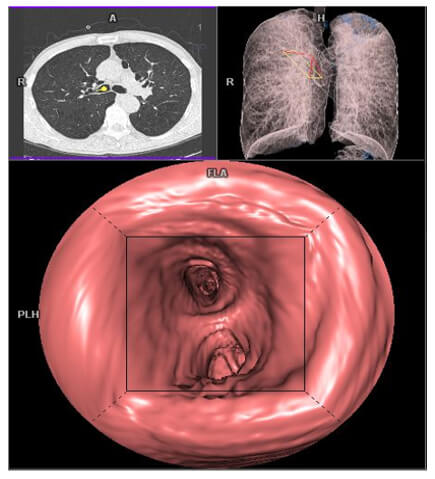

Bronchial Endoscopy

Bronchial endoscopy allows the visualization of the bronchial lumen filled with an inhalant object or invasive cancer. This is a 3D visualization of the interior of a hollow organ.